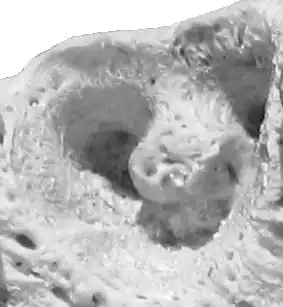

![]() Alveola of the second premolar tooth in a bovine maxillary bone | |

Dental alveoli (singular alveolus) are sockets in the jaws in which the roots of teeth are held in the alveolar process with the periodontal ligament. The lay term for dental alveoli is tooth sockets. A joint that connects the roots of the teeth and the alveolus is called a gomphosis (plural gomphoses). Alveolar bone is the bone that surrounds the roots of the teeth forming bone sockets.